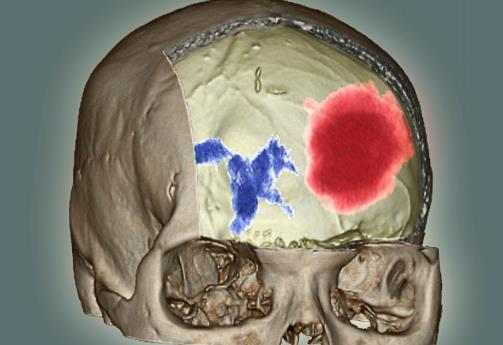

在了解脑出血的前兆之前我们先要看看什么是脑出血。脑溢血又称脑出血、发病急且进展迅速。数据显示在发生脑出血的患者中50%有先兆症状。脑溢血是指脑内微血管破裂出血是老年人的常见病好发于寒冷的冬季。常常表现为突然的一侧肢体麻木、无力或瘫痪,因此病人会在毫无防备的情况下跌倒或手中的物品突然掉地同时伴有口角歪斜、流口水、语言含糊不清或失语,严重者伴有意识障碍、大小便失禁等。病因多与高血压、动脉硬化有关具有起病急、后遗症多等特点对老人的危害很大是中老年人致死性疾病之一。